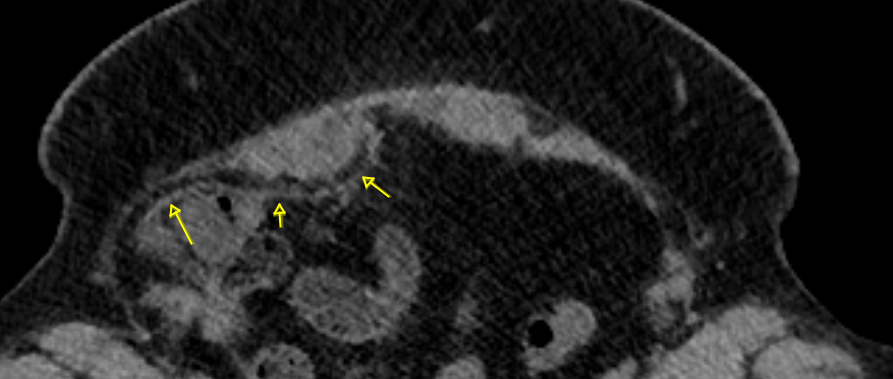

Filet au CT